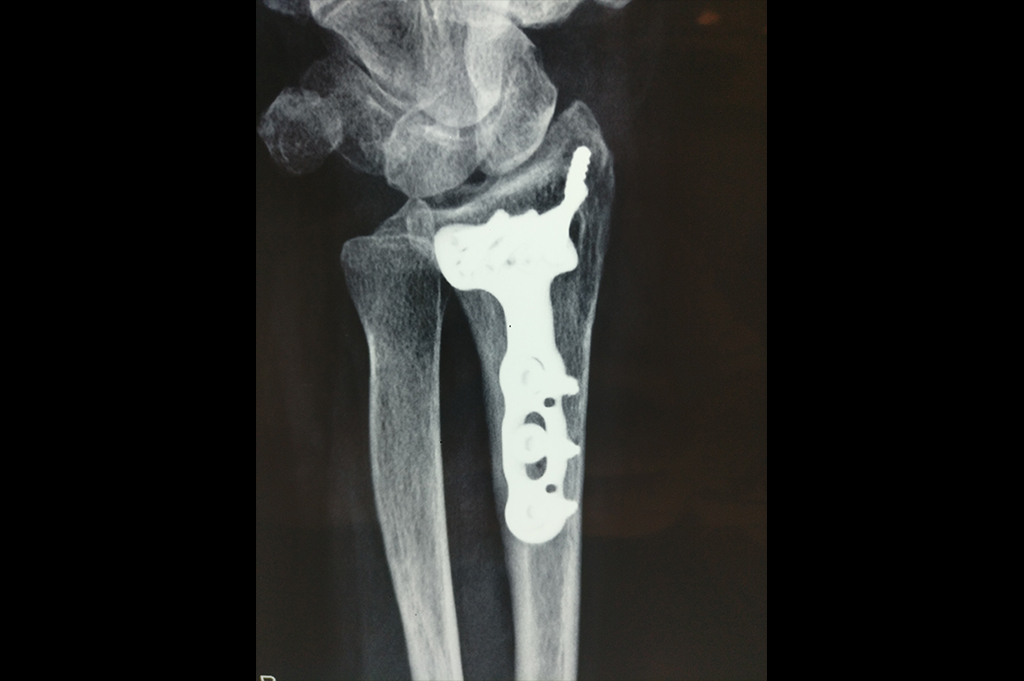

Osteoarthritis – High Tibial Osteotomy - HTO